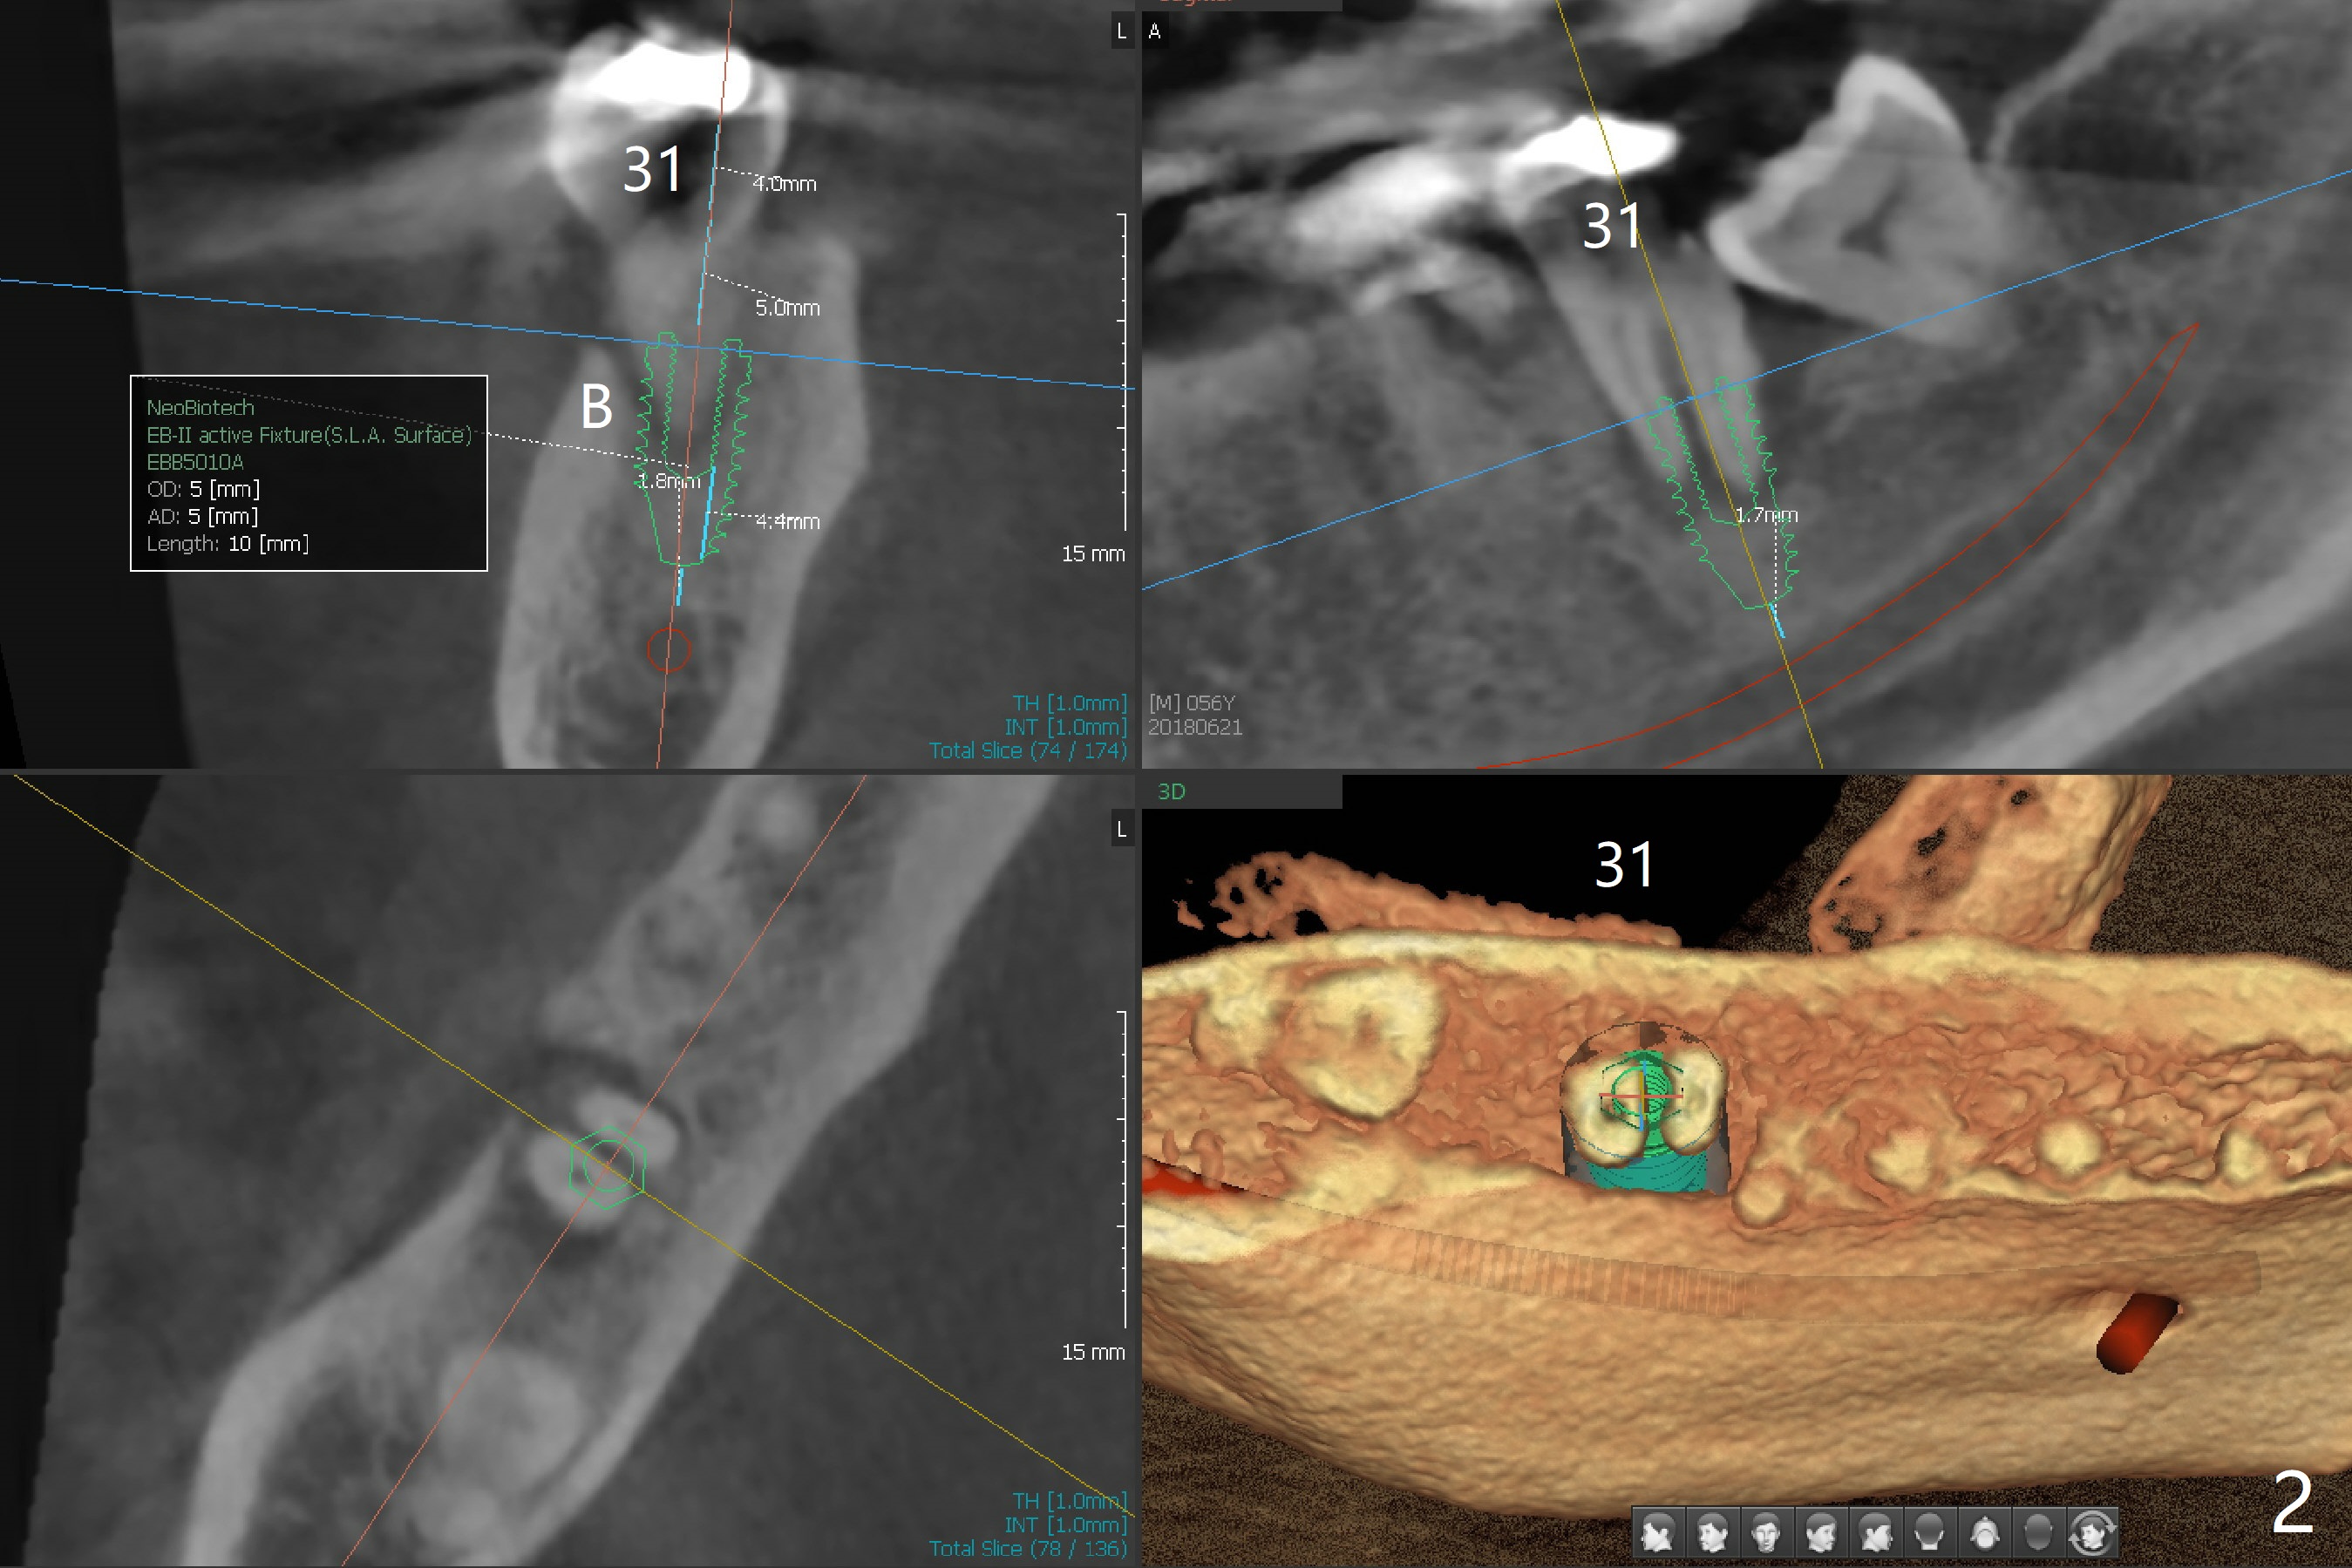

A 56-year-old man has complicated infection in the lower right posterior region (Fig.1). It appears that all of the molars need extraction. To alleviate financial burden, the teeth #31 and 32 will be first extracted with immediate implant at #31 (Fig.2).